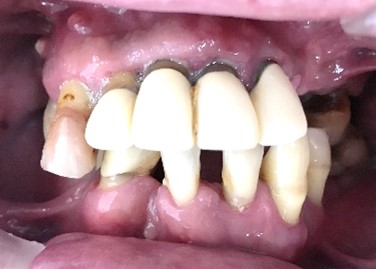

男性Iさん 50代(マグネット式入れ歯)

主訴

グラグラしている歯がある。歯並びをきれいにし、しっかり噛めるようになりたい。

治療内容

歯周病が進行し深刻な状態でした。保存することができない歯が上4本、下3本ありましたので、抜歯し、残った歯上4本、下7本の歯周病治療を徹底的にし、それらの歯を活用し上下マグネット式総入れ歯を入れました。

所感

治療前は、歯周病が進行し、重度に動揺している歯が4本あり、満足に食事ができない状況でした。マグネット式総入れ歯を装着後は、「なんでも思い通り噛むことができるだけでなく、歯並びもきれいになり、とても幸せです。」と、とても喜んでくださいました。

Before

赤丸は抜歯しました。上4本、下3本